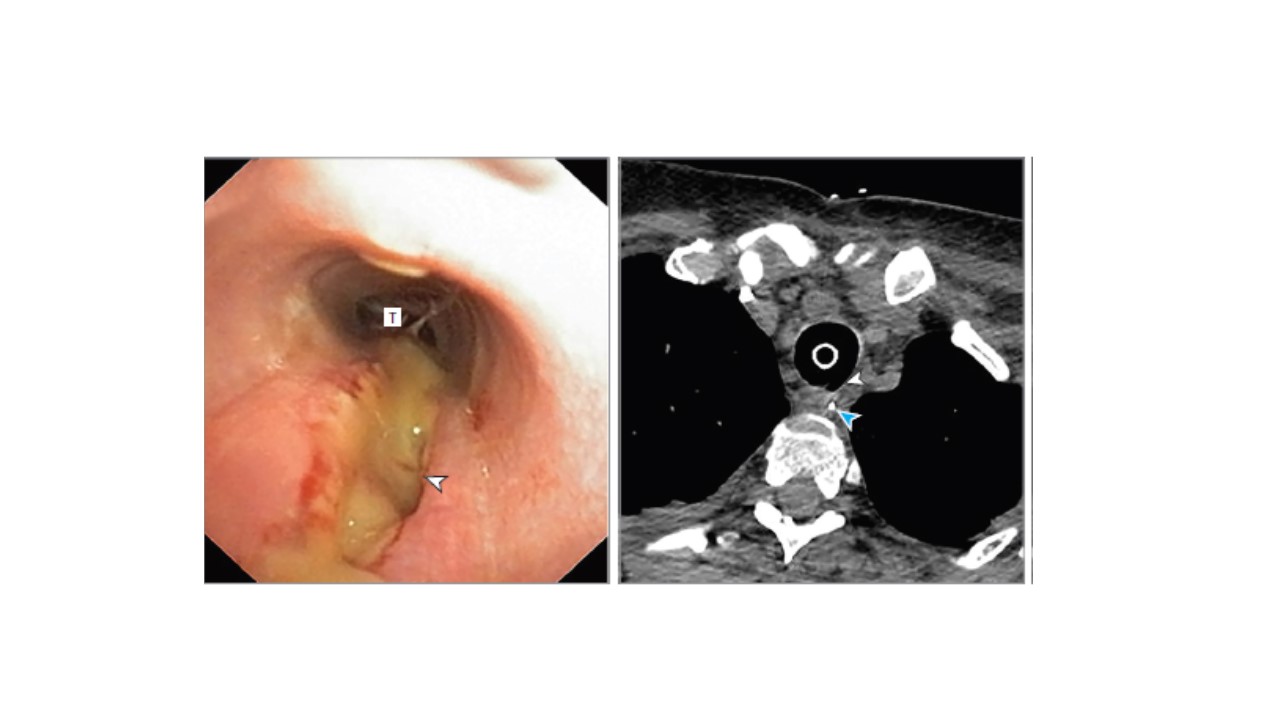

Il primo articolo - pubblicato sul Journal Thoracic and Cardiovascular Surgery (https://www.ncbi.nlm.nih.gov/pmc/articles/PMC7423512/) - presenta un complesso intervento di resezione laringo-tracheale a seguito di una grave stenosi laringo-tracheale dovuta alla complicanza di una tracheotomia in un paziente Covid. Lo studio evidenzia come la necrosi coagulativa sia presente nella mucosa delle alte vie respiratorie e in parte giustifichi l’elevata percentuale di complicanze nei pazienti Covid.

Il secondo articolo - pubblicato su Jama (https://pubmed.ncbi.nlm.nih.gov/33211087/) - ha mostrato come, su una larga coorte di pazienti intubati per Covid, l’incidenza di complicanze tracheali sia significativamente maggiore rispetto a un analogo periodo non-Covid.